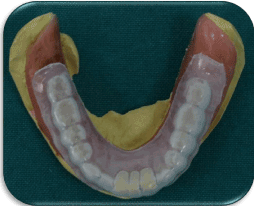

Figure 12. Pre-fabricated Clear Flexible Acrylic stent for Temporarization.